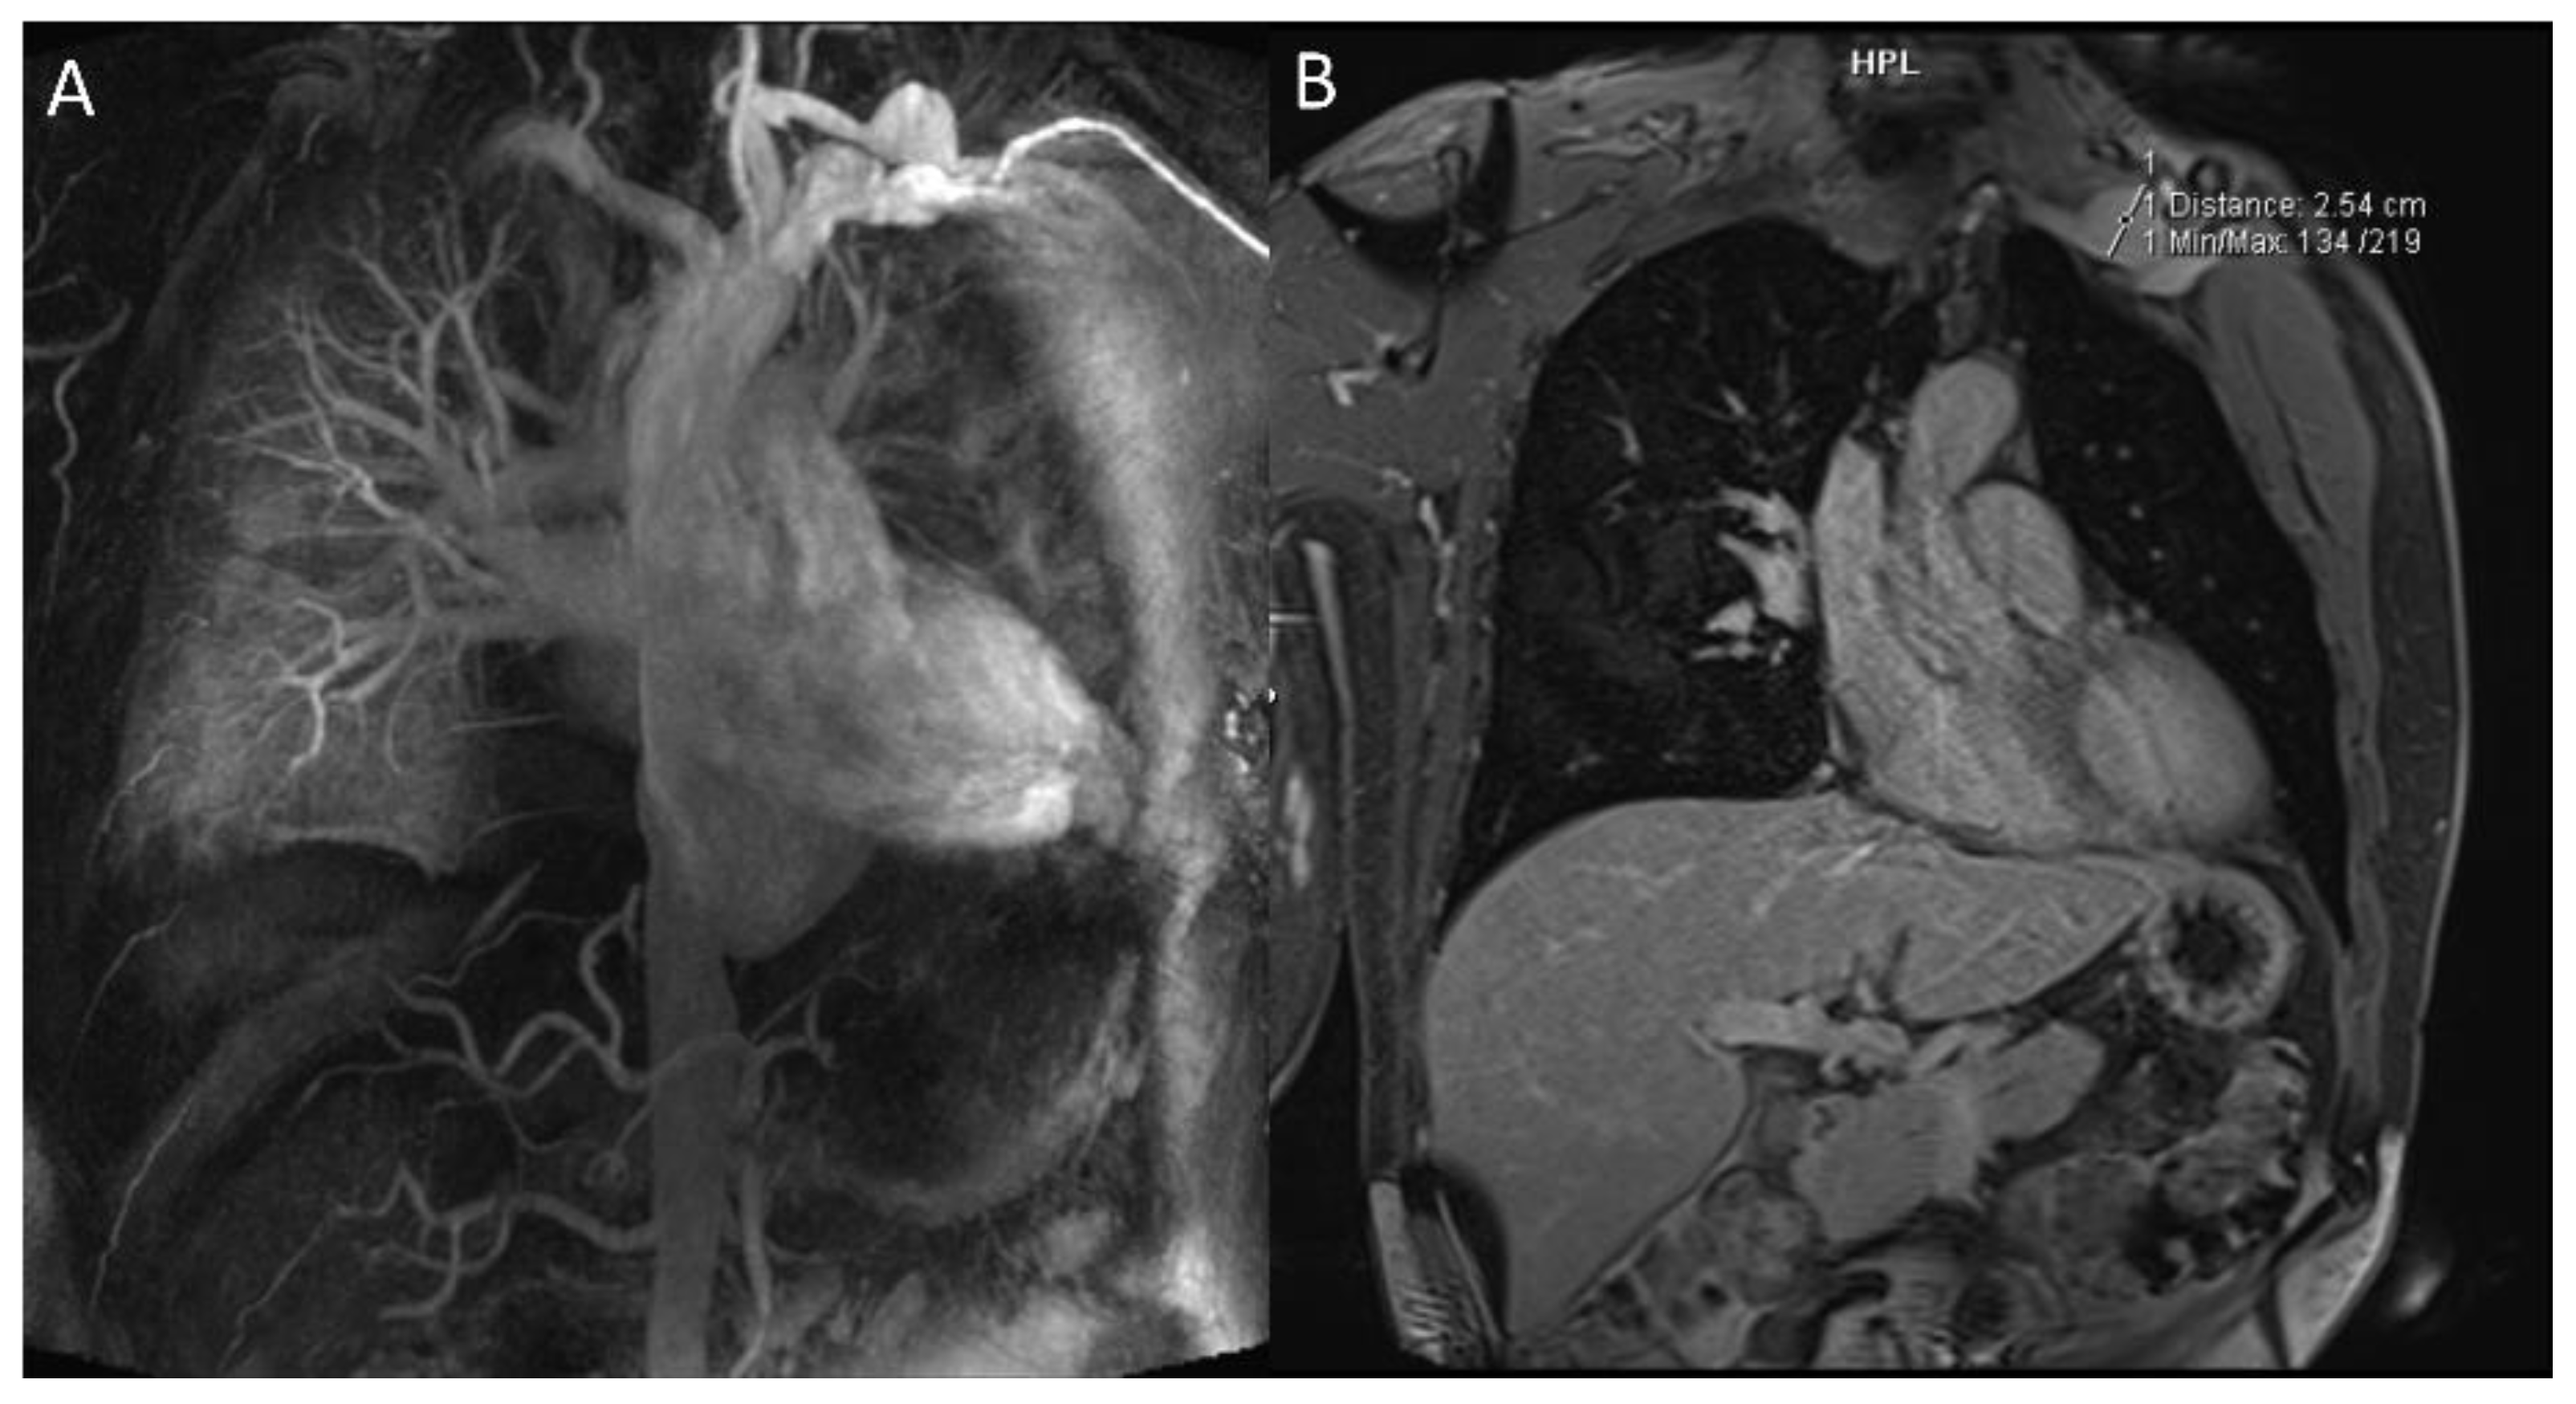

2.1.2. Pulmonary Arterial Manifestations

2.1.3. Systemic Veins

2.3. Mediastinum and Heart